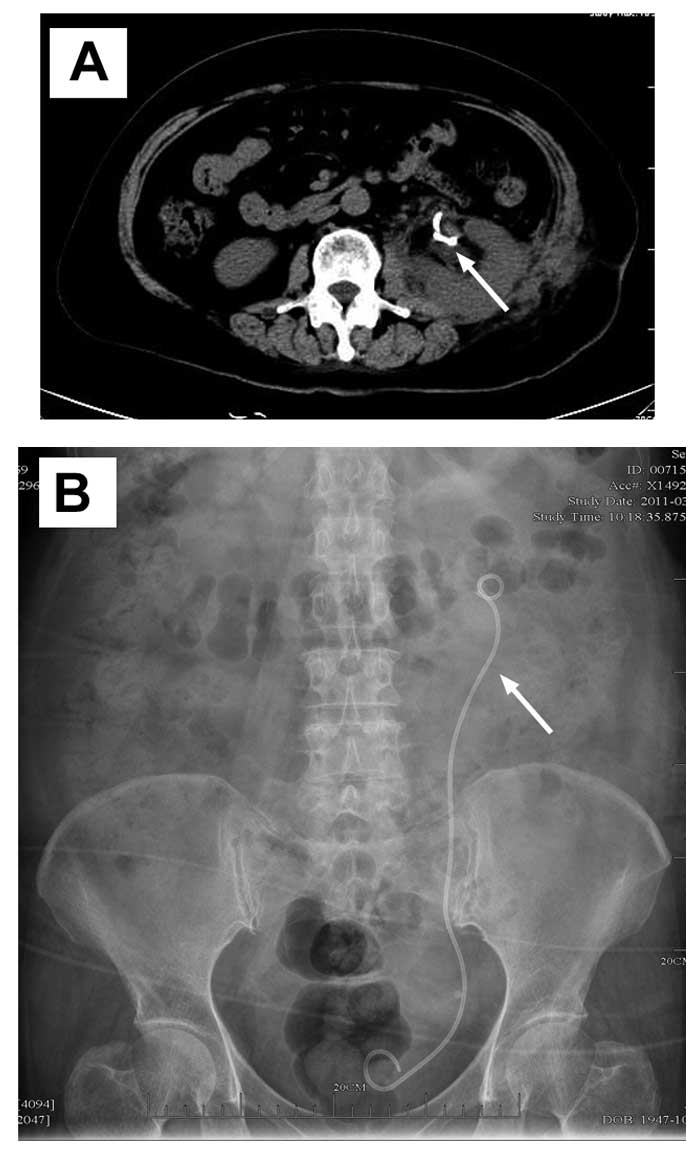

A 64-year-old female who had undergone PN in 2011 in The First Affiliated Hospital, Zhejiang University, Zhejiang, China for treatment of a tumour in the left kidney was admitted in February 2011 after 20 days of moderate left lower back pain. Imaging revealed two renal masses in the lower pole of the left kidney (Fig. 1). Following appropriate preoperative preparation, open PN was performed and the two masses were resected. The collection system was not opened during the surgery and the wounds were carefully closed with absorbable sutures. The wounds of the kidney were covered with perirenal fat and fibrin glue was used to adhere the fat to the kidney. The wounds were carefully sutured and a temporary drainage tube was placed near the left kidney. Pathological examination of surgical specimens revealed renal angiomyolipoma. The drainage tube was removed on the 5th postoperative day. The patient recovered completely and was discharged on the 7th postoperative day.

Figure 1

Preoperative imaging showing two renal masses in the lower pole of the left kidney. (A) Renal masses (arrow) were detected by ultrasound. (B and C) Renal masses (arrow) were detected by CT.